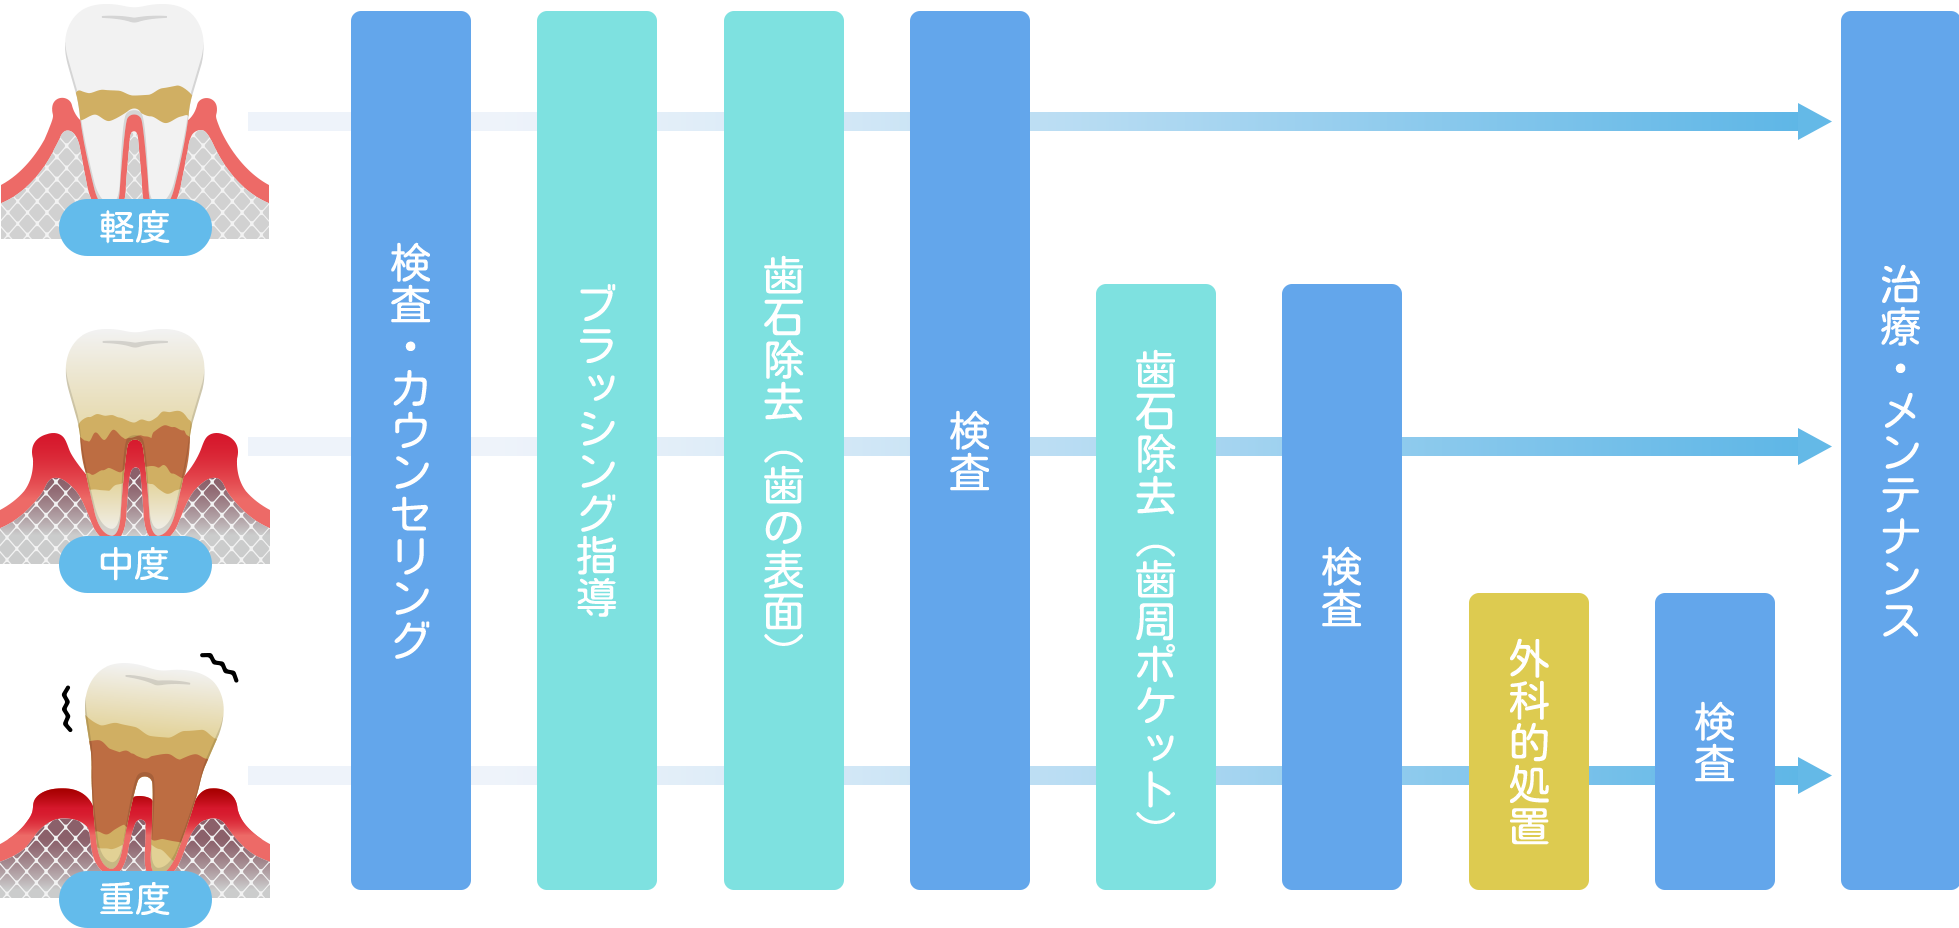

歯周病治療

歯科と二人三脚で

口腔内の細菌をコントロール

歯周病はその進行度によって、治療が異なりますが、口腔内の細菌の繁殖を抑えるためのメンテナンスによる口腔管理が治療の中心です。重度の場合や経過観察で回復が見られない場合には、歯茎を切開し歯槽骨に付着した汚れやダメージを受けた歯肉などを除去するフラップ手術を行います。

横スクロールで確認いただけます。